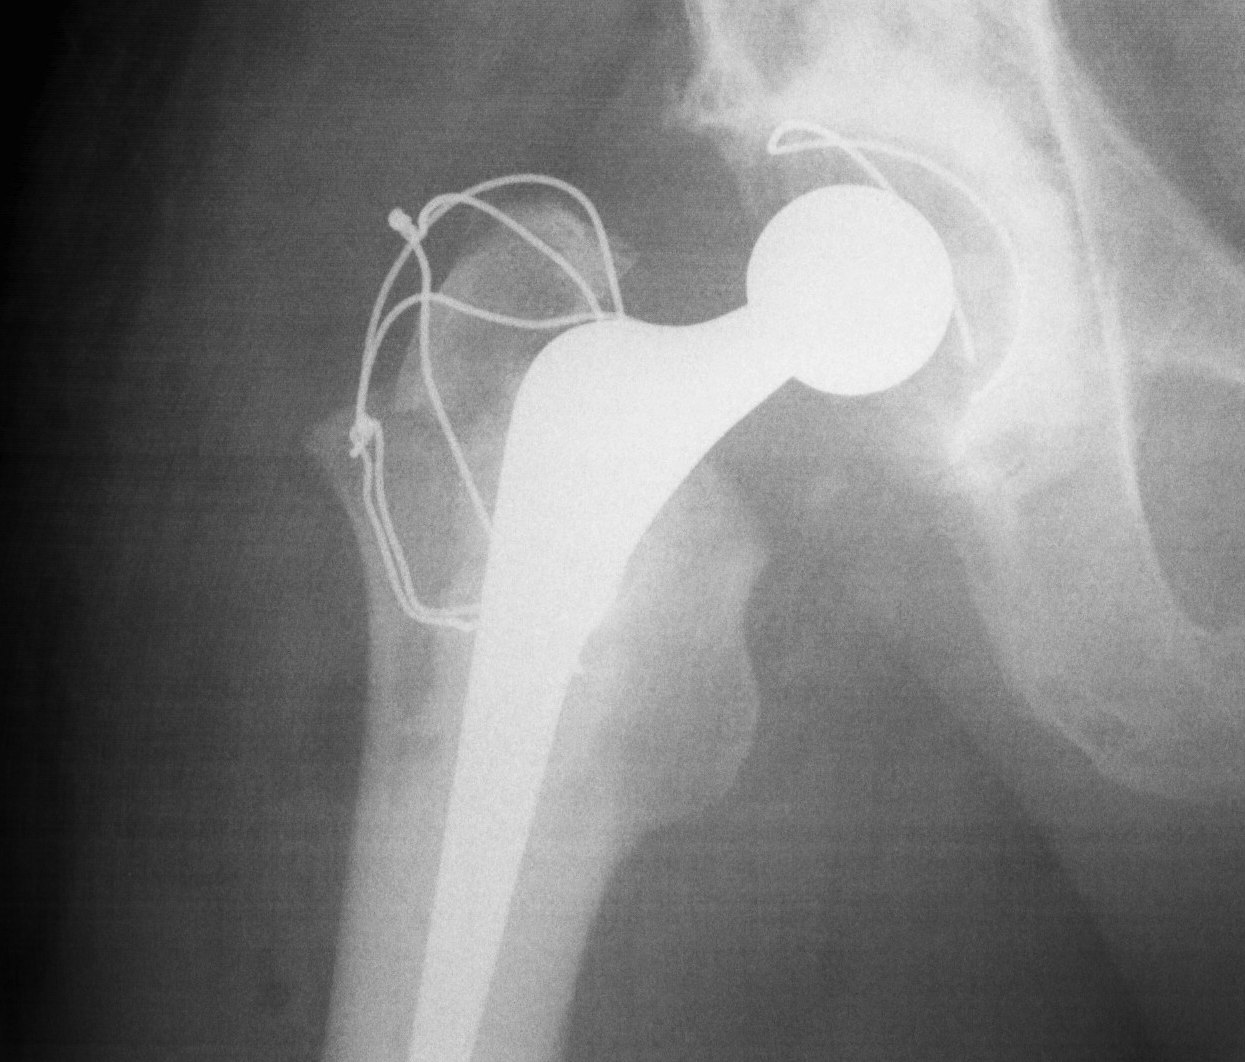

Trochanteric Osteotomy

Types

1. Standard trochanteric osteotomy

2. Sliding trochanteric osteotomy

3. Extended trochanteric osteotomy